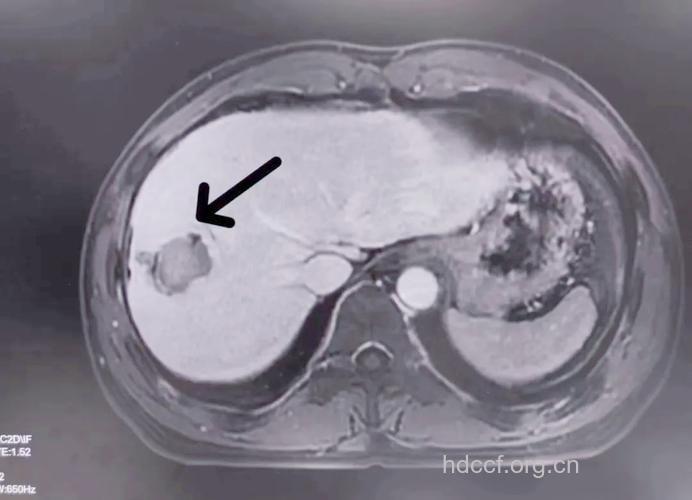

MRI无放射性辐射,可从多个方位进行成像。新型的MRI已经克服了早期成像速度太慢的缺点,场强提高到1.5~2.0T,使得多种新的成像技术如梯度回波序列及波谱分析等得以实现,加上肝细胞特异性造影剂的应用,对小肝癌的检出率大大提高,小于1cm的病灶检出率为55%,1~2cm为70%,2~3cm达82%。MRI能清晰显示肝内血管和胆管结构,对了解肿瘤与肝内血管胆管的关系有很大帮助。MRI还能较好地显示肝脏和肝癌组织的内部结构,对评估各种治疗疗效很有帮助,如经皮瘤内酒精注射术、射频消融术或微波固化术后,肿瘤坏死在T2期显示为均匀的低信号,如果肿瘤内部信号不均匀,则常常提示治疗后坏死不完全。MRI易于发现位于肝表面CT难以检测到的小肝癌,对肝内小转移灶的敏感性亦颇高,但肝左叶边缘受心脏及主动脉搏动的影响而小肝癌检出率与CT相差不大。

CT的出现使肝癌影像学诊断有了一个质的飞跃,并带动了肝脏外科的进步。CT的分辩率远远高于超声,图像更加清晰和稳定,更能全面客观地反映肝癌的特性。CT检查可清楚地显示肝癌的大小、数目、形态、部位、边界、肿瘤血供丰富程度,以及与肝内管道的关系;对门静脉、肝静脉和下腔静脉是否有癌栓,肝门和腹腔淋巴结是否有转移,肝癌是否侵犯邻近组织器官都有很重要的诊断价值;CT还可通过显示肝脏的外形、脾脏的大小以及有无腹水来判断肝硬化的轻重。快速螺旋CT能在一次屏气(20s左右)即可完成整个肝脏的扫描,可避免呼吸运动所致层面的上下移动而漏扫微小病灶,还可克服呼吸运动产生的伪影问题。螺旋CT最小可用1mm的层厚进行薄层扫描,对1~3cm的小肝癌检出率可达90%,并能在螺旋扫描的长度内实施高质量的三维图像重建。对增强CT难以作出明确诊断的肝癌,还可进一步采用血管造影CT。经皮导管在肝动脉注入造影剂,观察肝动脉显影时的CT,称CT血管造影。